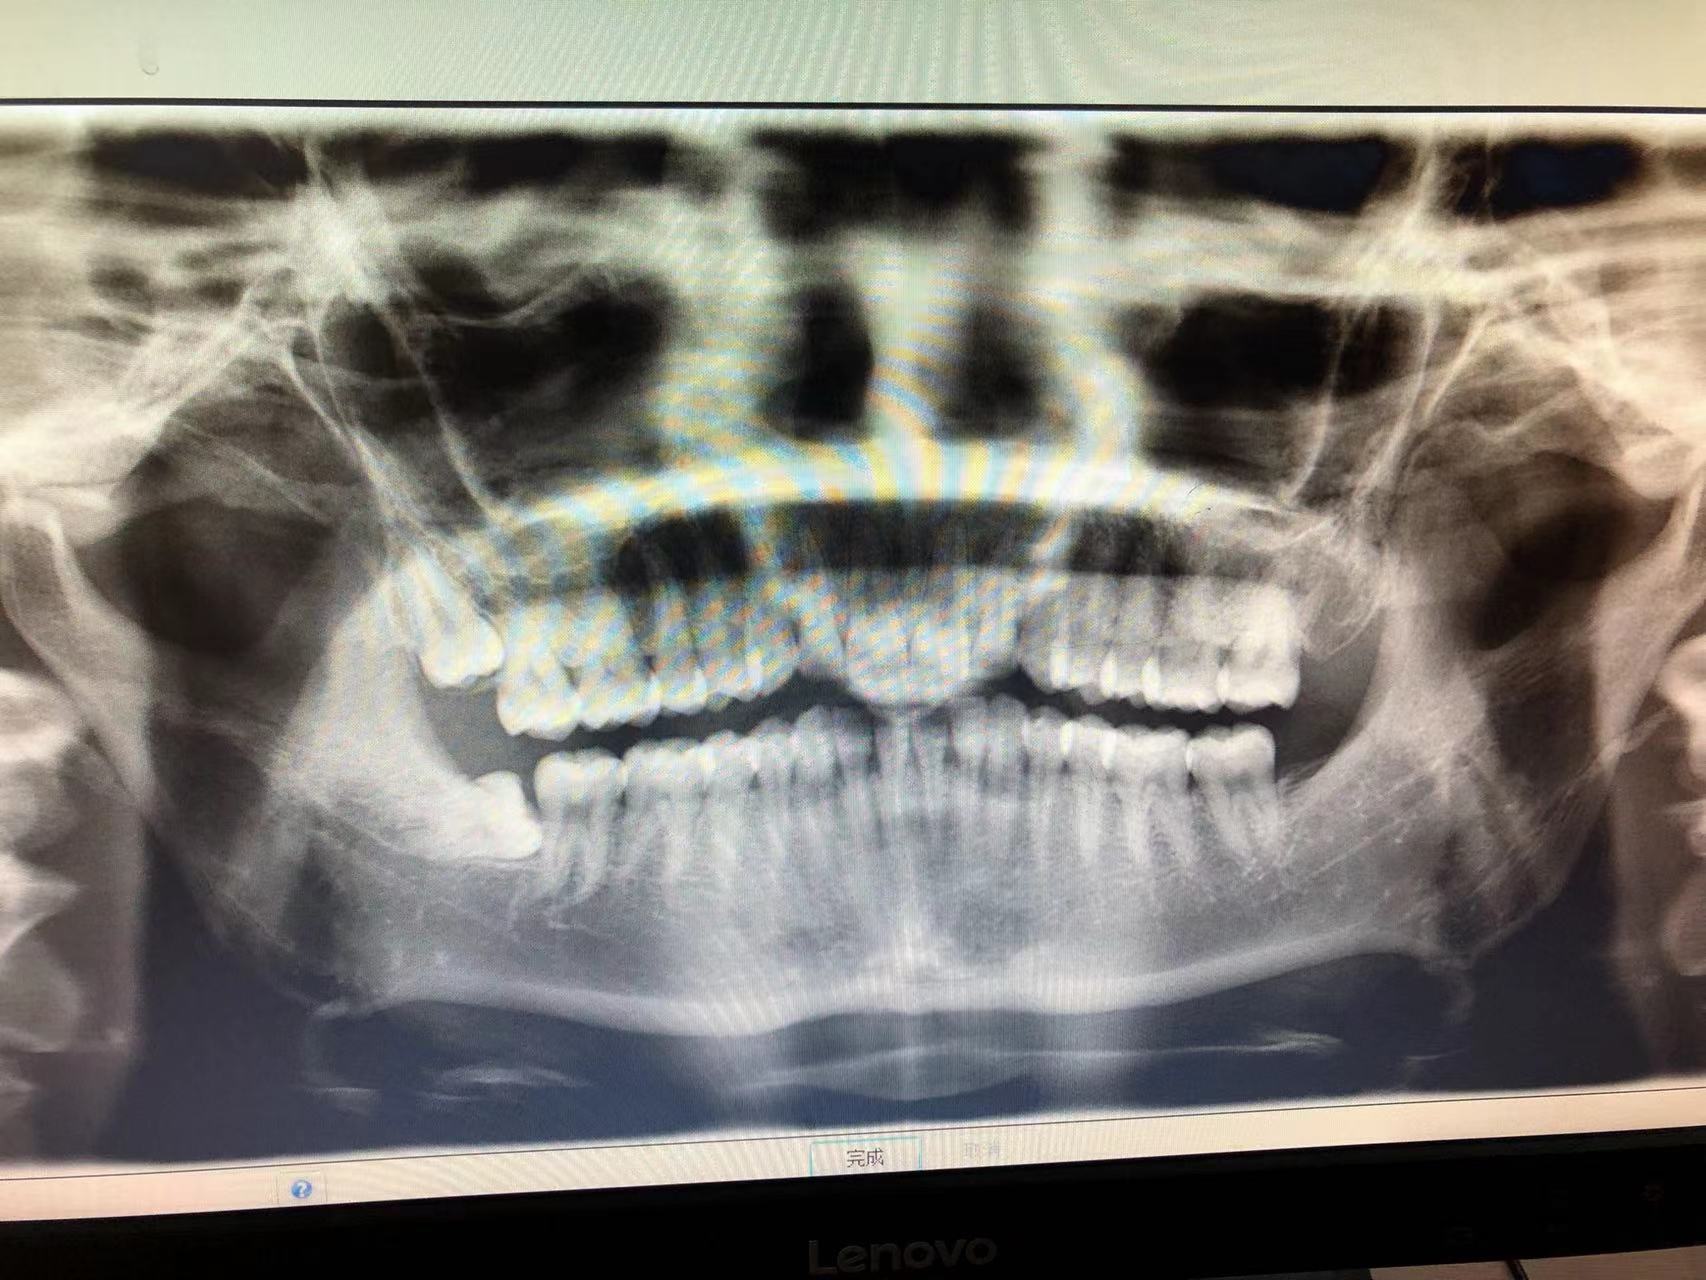

先去的北航校医院,拍了一个口腔ct,然后医生跟我说,建议我去北医三院拔,于是开始了每天早上7点的预约抢号(北医三院每天早上7点准时开放接下来三天的号源!!!)。

第一次抢到了一个普通号,等我现场看诊的时候,医生告诉我需要挂牙槽外科的专号,这个医生人特别好,先给我开了一个医院的口腔ct,然后又告诉我可以预约哪位医生,可以预约哪一天,由于号时间比较久,我决定自己挂号。

轮到我的号时,刘政文医生调出了我的ct,然后说了一些注意细节,助理医生检查了一下核酸(北医三院口腔科需要48小时核酸才可以看诊)因为我是右边上下各长了一颗阻生牙(智齿),于是,刘医生建议我先把一颗简单的,就开始了,大概才10分钟左右就结束了。